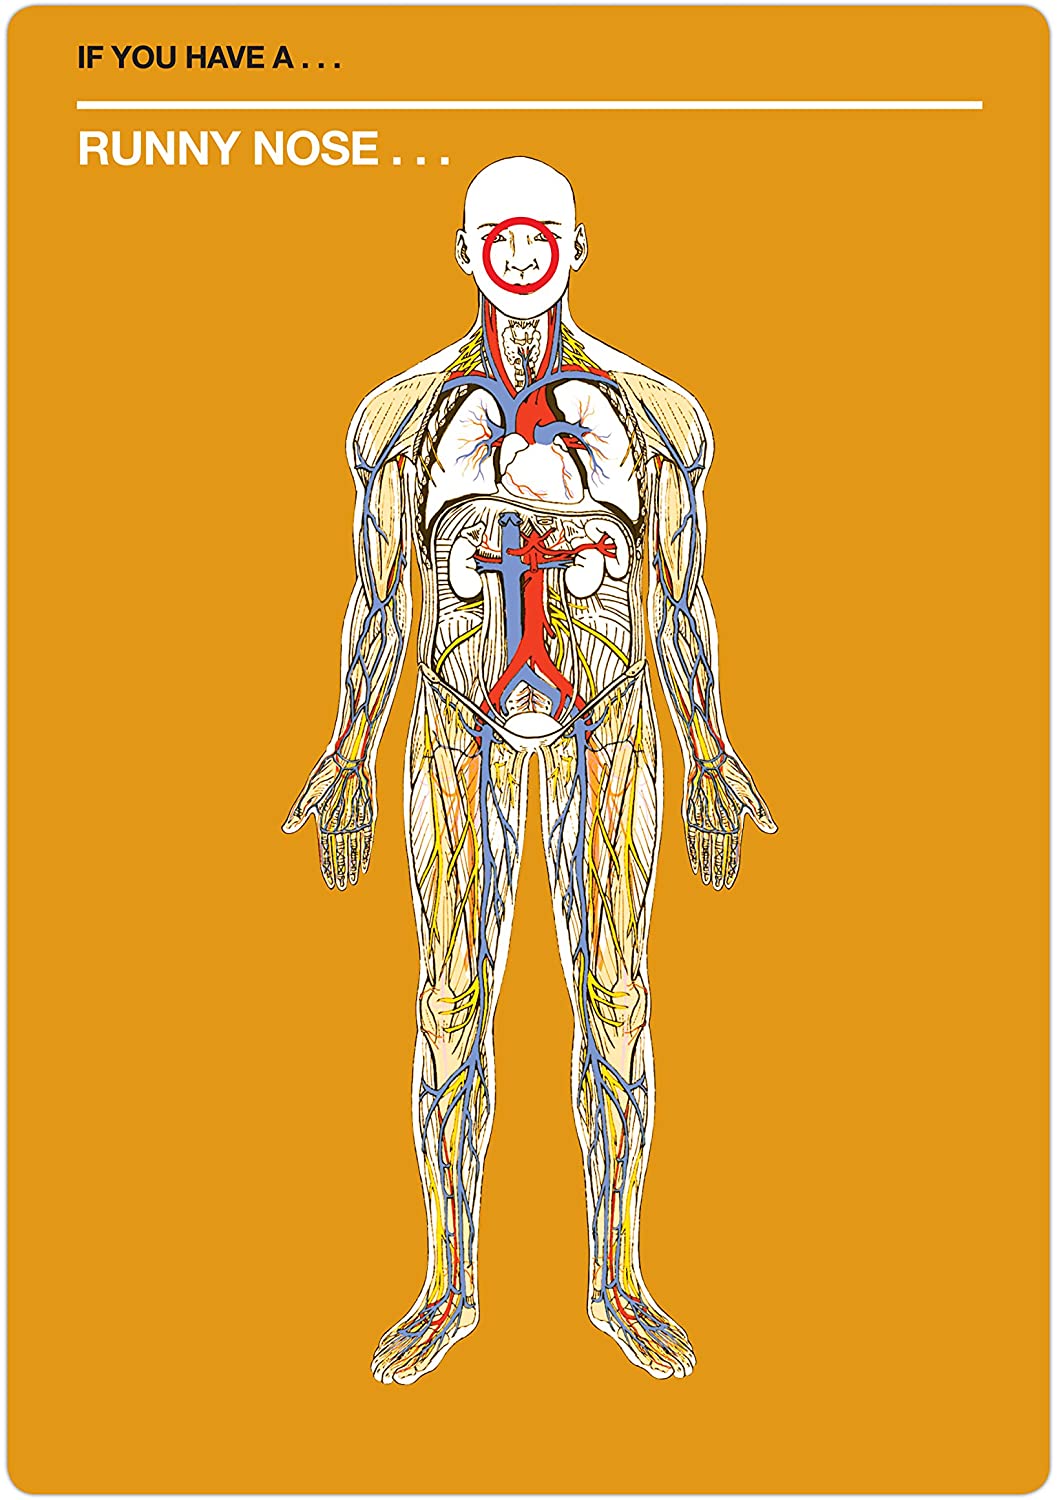

- With this deck of Fifty Things That Might Kill You, pick your symptom and pick a card (or cards) to see what rare, multisyllabic, and possibly fatal disease you might have

- A symptom checker that mixes dark humor (and actual facts) for hypochondriac fun!